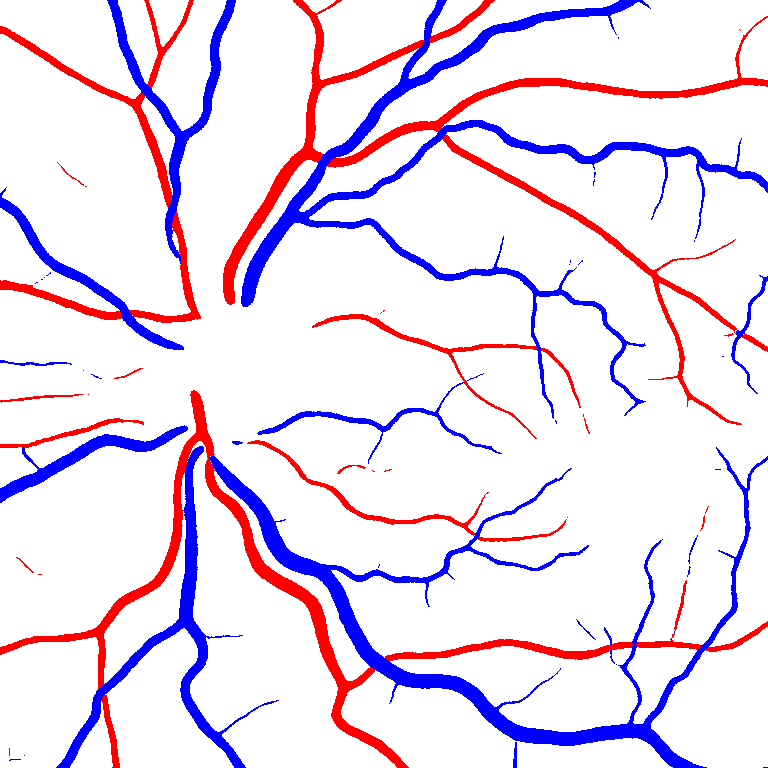

As reported in Table IV, we compared the SegRAVIR model against competing deep learning-based segmentation approaches on the RAVIR dataset. Evidently, SegRAVIR outperforms these methods as judged by all metrics for artery and vein classes with a healthy margin. In terms of Dice score, SegRAVIR outperforms CE-NET, IterNet and AG-Net by , and for artery segmentation and by , and for vein segmentation, respectively. Fig. 4 presents a qualitative comparison of the semantic segmentation outputs of SegRAVIR, CE-Net, and U-Net. Specifically, SegRAVIR yields more accurate vessel topology (i.e., thickness and orientation) segmentation with higher pixel-wise classification accuracy.

Table V presents quantitative performance benchmarks of SegRAVIR and other competing approaches for retinal artery and vein classification on the RITE dataset [11]. SegRAVIR outperforms previous state-of-the-art approaches in terms of accuracy, sensitivity, and specificity. Fig. 5 provides a qualitative comparison between segmentation outputs of SegRAVIR and the method of Hemelings et al. [40] on the RITE test set.